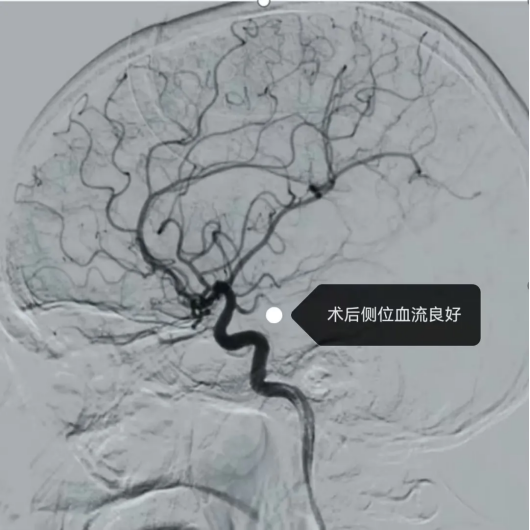

(术中、后影像)

最终,在团队娴熟配合与精准操作下,手术顺利完成。术后患者肢体肌力及语言功能均恢复良好,NIHSS评分显著改善,目前已基本恢复正常生活能力,治疗效果良好。